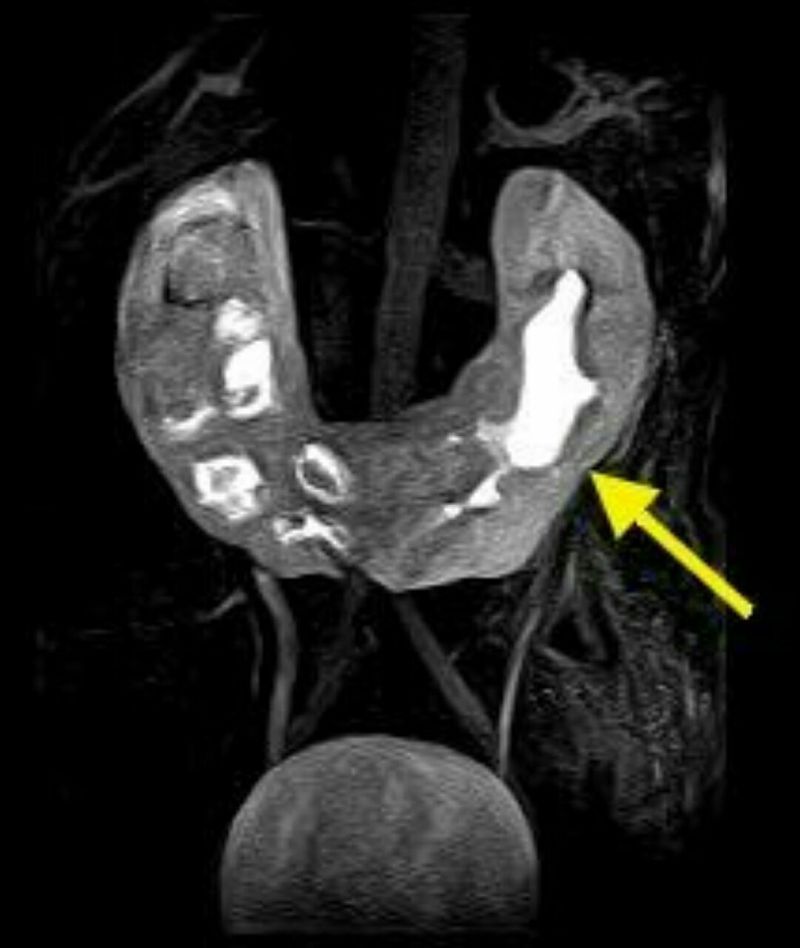

Horseshoe kidney, also known as renal fusion is a congenital disorder affecting about 1 in 500 people that is more common in men, often asymptomatic, and usually diagnosed incidentally. In this disorder, the patient's kidneys fuse together to form a horseshoe - shape during development in the womb. The fused part is the isthmus of the horseshoe kidney.